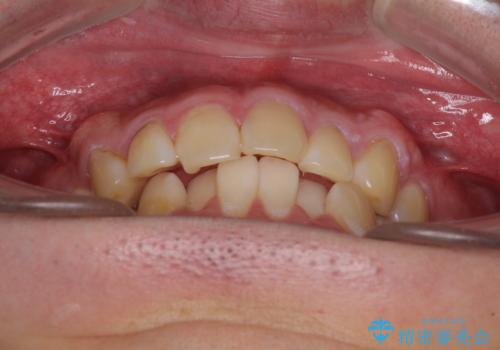

- 上下前歯のデコボコを気にして来院された患者様です。

前歯のデコボコ以外に左側の奥歯の咬み合わせに問題がありましたが、価格を抑え、短期間で気になる前歯を治したいとのことでした。

こちらの患者様は、事前のシミュレーションにより、インビザライン・ライトでは前歯のデコボコを解消しきれないことが分かったため、通常のインビザライン(コンプリヘンシブパッケージ)での治療が必要となりました。